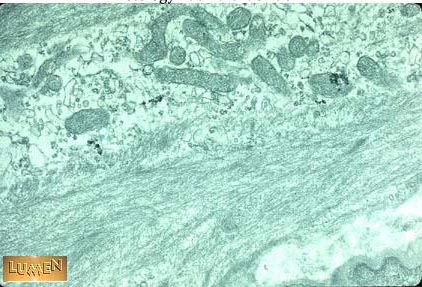

Name the protein that is necessary for the contraction of this cell.

Answer

Calmodulin-dependent myosin

light chain kinase